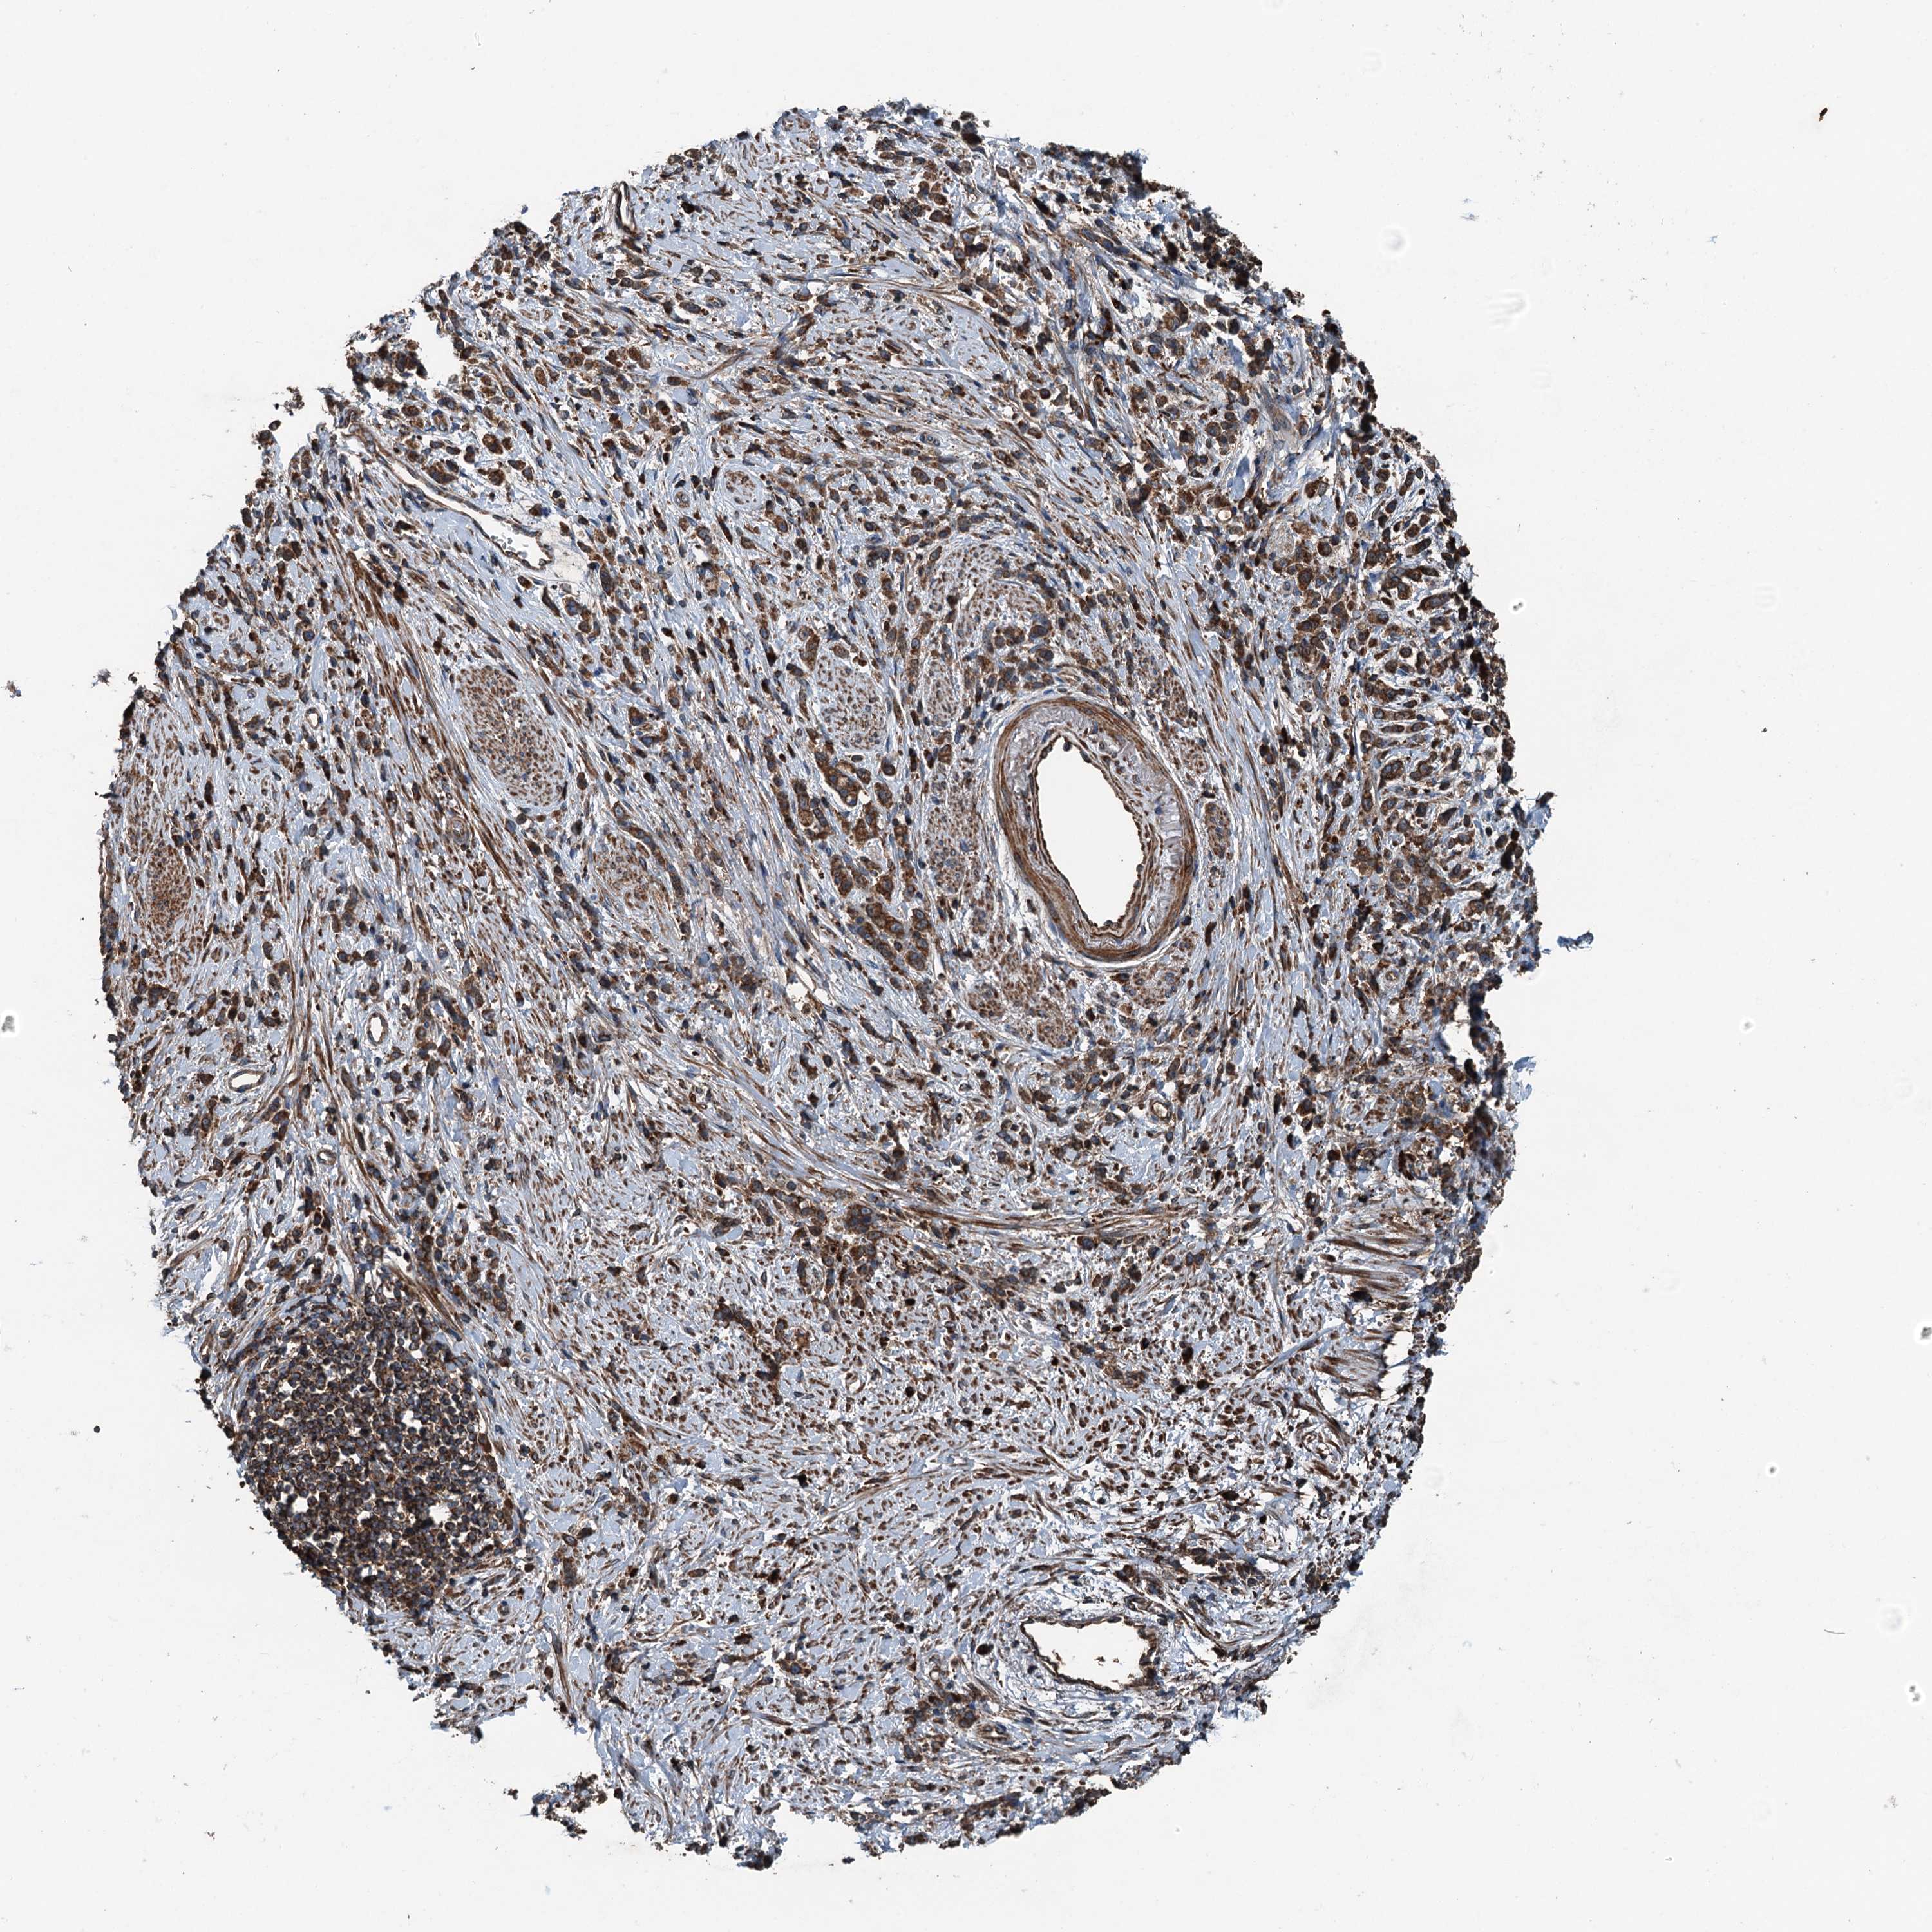

STOMACH CANCER - Protein expressioni

A mouse-over function shows sample information and annotation data. Click on an image to view it in a full screen mode. Samples can be filtered based on level of antibody staining by selecting one or several of the following categories: high, medium, low and not detected. The assay and annotation is described here.

Note that samples used for immunohistochemistry by the Human Protein Atlas do not correspond to samples in the TCGA dataset.

Antibody stainingi

Antibody staining in the annotated cell types in the current human tissue is reported as not detected, low, medium, or high, based on conventional immunohistochemistry profiling in selected tissues. This score is based on the combination of the staining intensity and fraction of stained cells.

Each image is clickable and will lead to virtual microscopy that enables deeper exploration of all samples and also displays staining intensity scores, fraction scores and subcellular localization as well as patient and tissue information for each sample.

Antibody HPA041227

Staining

High

Medium

Low

Not detected

Intensity

Strong

Moderate

Weak

Negative

Quantity

>75%

75%-25%

<25%

None

Location

Nuclear

Cytoplasmic/membranous

Cytoplasmic/membranous,nuclear

Adenocarcinoma, NOS

Adenocarcinoma, High grade